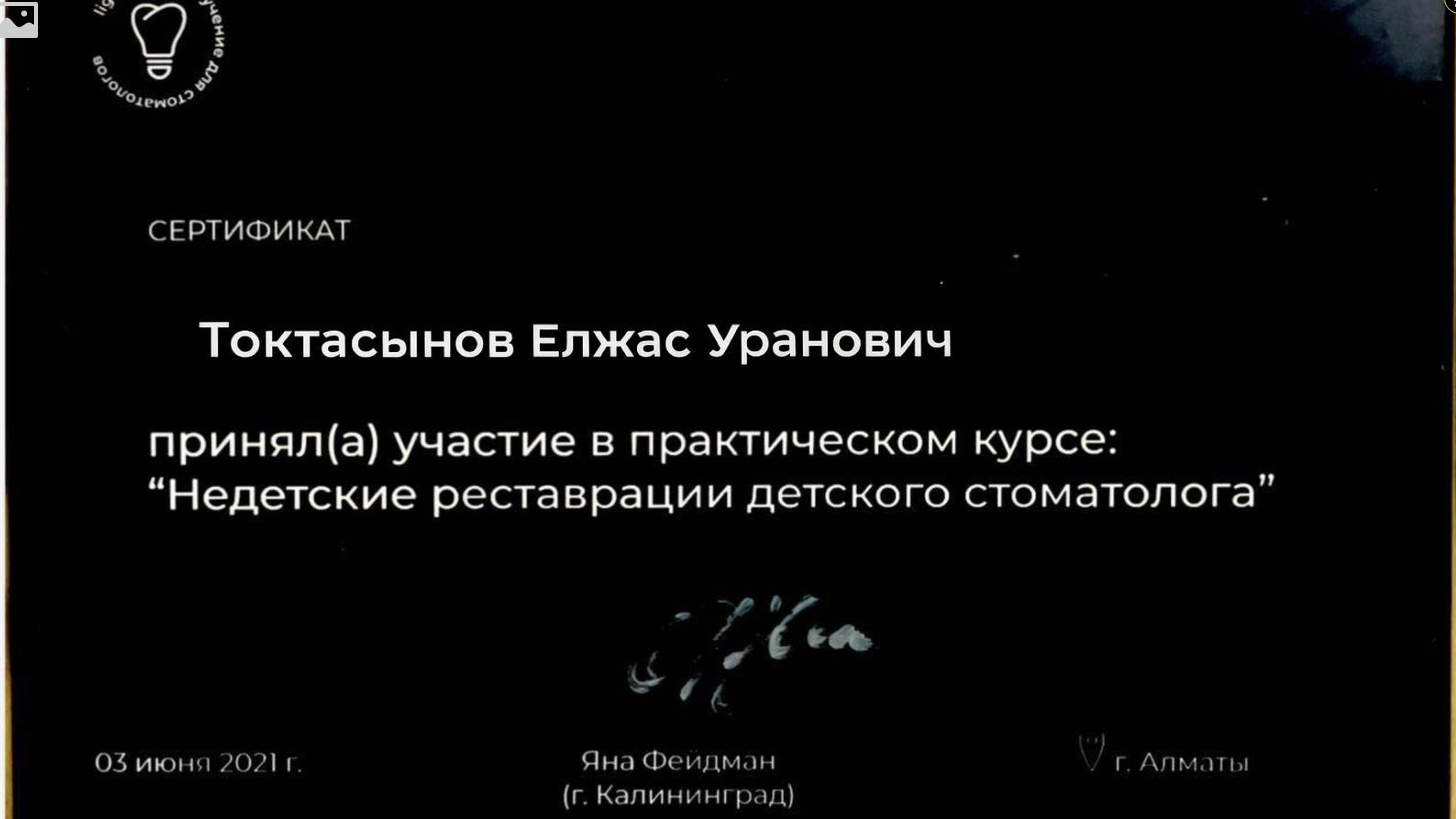

Токтасынов Елжас Уранович

Выпускник Казахского национального медицинского университета им. С. Д. Асфендиярова, интернатура с отличием

Специализация: лечение кариеса, пульпита и периодонтита временных зубов, эстетическая реставрация и профилактика